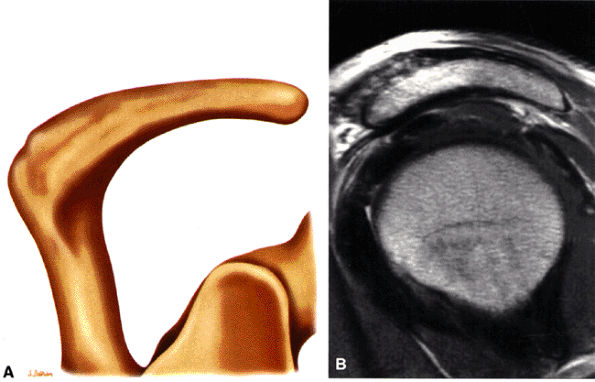

The acromion is classified into several types according to its morphology:

Type 1 (a flat or straight undersurface with a high angle of inclination)

Type 2 (a curved arc and decreased angle of inclination)

Type 3 (hooked anteriorly with a decreased angle of inclination)

Type 4 (upward convexity of the inferior surface) (see also the discussion of the etiology of shoulder impingement syndrome)